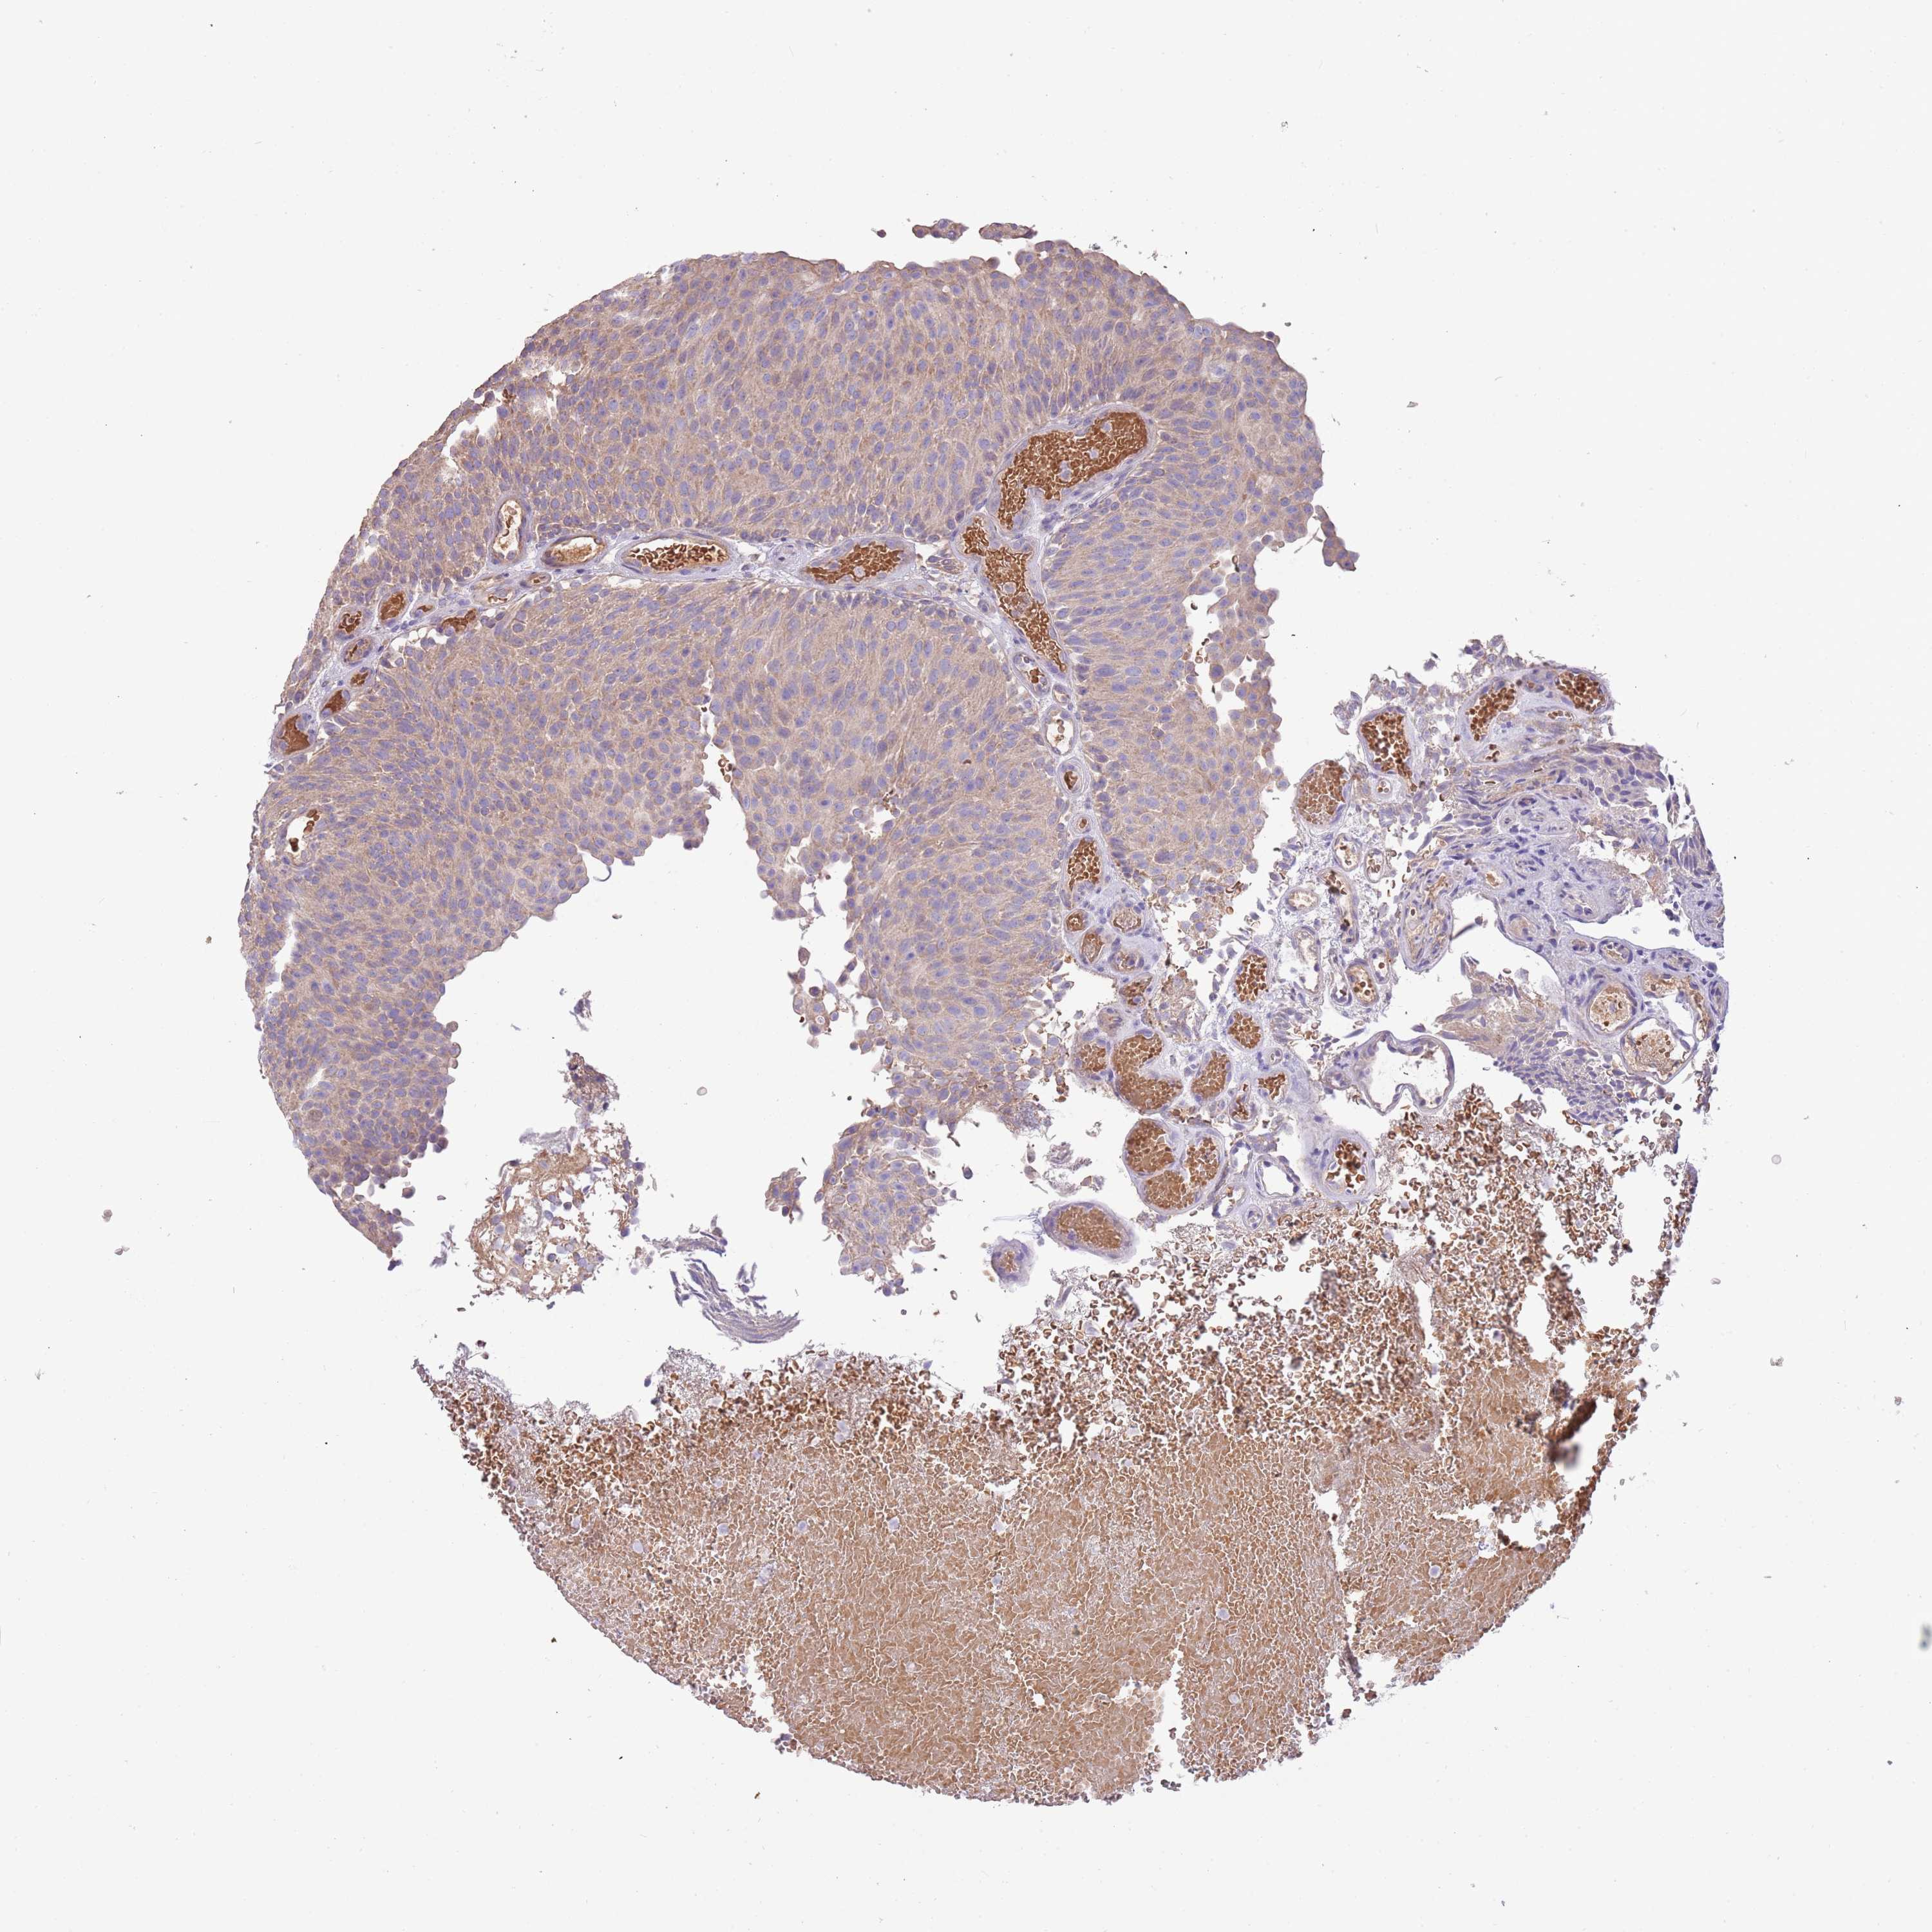

UROTHELIAL CANCER - Protein expressioni

A mouse-over function shows sample information and annotation data. Click on an image to view it in a full screen mode. Samples can be filtered based on level of antibody staining by selecting one or several of the following categories: high, medium, low and not detected. The assay and annotation is described here.

Note that samples used for immunohistochemistry by the Human Protein Atlas do not correspond to samples in the TCGA dataset.

Antibody stainingi

Antibody staining in the annotated cell types in the current human tissue is reported as not detected, low, medium, or high, based on conventional immunohistochemistry profiling in selected tissues. This score is based on the combination of the staining intensity and fraction of stained cells.

Each image is clickable and will lead to virtual microscopy that enables deeper exploration of all samples and also displays staining intensity scores, fraction scores and subcellular localization as well as patient and tissue information for each sample.

Antibody HPA021281

Staining

High

Medium

Low

Not detected

Intensity

Strong

Moderate

Weak

Negative

Quantity

>75%

75%-25%

<25%

None

Location

Nuclear

Cytoplasmic/membranous

Cytoplasmic/membranous,nuclear

Urothelial carcinoma, Low grade

Urothelial carcinoma, High grade

Urothelial carcinoma, NOS